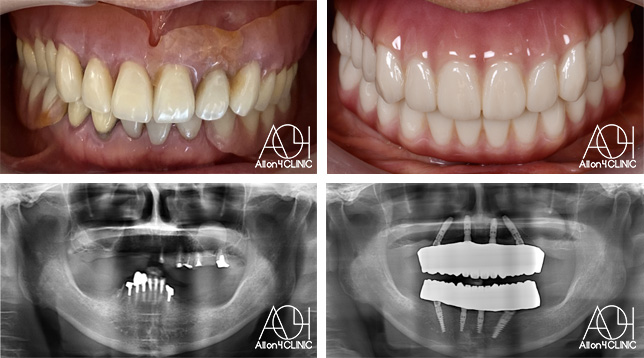

Treatment : All-on-4

- Upper All-on-4

- Lower All-on-4

Age : 62 Sex : 女 Y.M

| 主訴 | 入れ歯が合わなく痛いし、入れ歯を入れている事が嫌になってしまった。 |

| 治療内容 | X-guide(エックスガイドナビゲーションシステム)を用いてインプラントを正確に埋入。 上下オールオン4。 |

| 治療費(総額) | ¥7,200,000(税抜)『モニター割引適用』 |

| リスク | 治療後の口腔管理が不適切な場合、埋入したインプラント周囲に感染・炎症を起こし、脱落する可能性がございます。 |